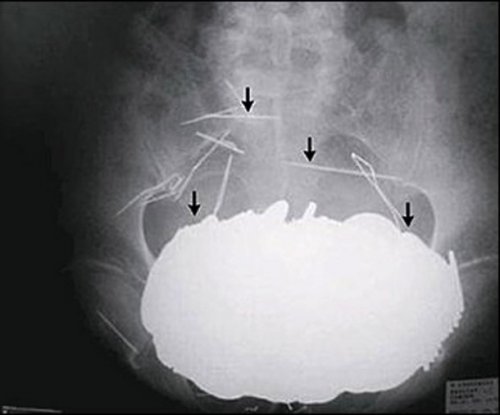

Бутерброды с бананом, картошка фри с молочным коктейлем, соленья с арахисовым маслом... У некоторых людей есть необычные привычки питания и предпочтения в еде. Однако после прочтения этой статьи вы сочтёте эти маленькие отклонения абсолютно приемлемыми. Ознакомьтесь с этими странными предметами, которые были найдены в человеческом кишечнике (которые, вероятно, заставили поёжиться даже самых опытных хирургов). 25. Бутылка Мужчина обратился в китайскую больницу с жалобами на боли в животе. То, что врачи обнаружили, было шокирующим и довольно смущающим для бедолаги. Оказалось, причиной брюшной боли была бутылка, которую удалили хирургическим путём. 24. Столовые приборы Маргарет Далман (Margaret Daalman) из Нидерландов попала в больницу с болями в желудке. Хирурги в Роттердамской больнице отправили её на рентген и были потрясены, когда изображение показало 78 различных предметов столовых приборов в желудке 52-летней женщины. К счастью, она ела только ложки и вилки, а не ножи. 23. Батарейки Каждый год регистрируется несколько случаев, когда дети съедают батарейки. К примеру, в декабре 2013 года 13-месячный мальчик из города Лестер (Leicester), Англия, умер от внутреннего кровотечения после проглатывания батарейки, которую он нашёл в своём детском саду. 22. Живые лягушки Янг Дингкай (Yang Dingcai) с юго-востока Китая говорит, что 40-летняя привычка глотания живых лягушек и крыс помогла ему избежать проблем с кишечником и сделала его сильным. 21. Гвоздь Китайский плотник Ли Сянъян (Li Xiangyang) держал гвоздь между своих зубов, когда он вдруг закашлялся и проглотил его. Он был доставлен в больницу, где врачи сделали рентгеновский снимок и нашли гвоздь в правом лёгком. Профессор Ху Кэ (Hu Ke) попытался удалить его с помощью бронхоскопа через его горло. Однако в тот момент, когда он был уже на грани того, чтобы вытянуть гвоздь, Ли снова закашлялся и всосал его обратно. На этот раз гвоздь оказался в его левом лёгком. Ху попытался снова, но в последнюю минуту, Ли невольно сглотнул и гвоздь снова исчез. В конце концов, врачи обнаружили гвоздь и, наконец, смогли удалить его с помощью гастроскопического зажима. 20. Ручная граната Рентген выявил ручную гранату в желудке террориста. Очевидно, он не продумал свой план достаточно хорошо, потому что у него не было возможности на самом деле детонировать гранату. 19. Ложка 33-летняя женщина пыталась ложкой удалить рыбную кость, попавшую в её гортань. Она случайно проглотила ложку, и её пришлось отвезти прямиком в операционную, чтобы удалить ложку хирургическим путём. 18. Пуля Четырёхлетняя девочка из города Тхане (Thane), Индия, проглотила пулю в районе Локманья Нагар (Lokmanya Nagar). Девочка играла в окрестности, когда она нашла пулю, лежавшую на земле. Предположив, что это был шоколад, она взяла её и положила в рот. Девочку отвезли в больницу, где врачам удалось успешно вытащить свинец без хирургического вмешательства. 17. Наркотики Нигерийца, пойманного в Международном аэропорту Куала-Лумпур (Kuala Lumpur International Airport) в Малайзии, доставили в больницу, где рентген показал наличие инородного предмета в его желудке. Предметом, как оказалось позднее, были 54 капсулы метамфетамина. 16. Живой угорь Мужчина из Китая обратился в больницу после того, как по сообщениям, в нём застрял живой угорь. Мужчина вставил 50-сантиметрового азиатского рисового угря себе в анус, увидев, как это сделали в порно. Поэтому ему пришлось выдержать операцию, которая длилась всю ночь, чтобы извлечь этого угря. Как сообщается, члены команды врачей сказали, что угорь, который «просто пытался найти выход», был жив, когда его вытащили, но вскоре скончался. 15. Обручальное кольцо Кейтлин Уиппл (Kaitlin Whipple) проглотила обручальное кольцо, которое её бойфренд Рид Харрис (Reed Harris) поставил в её мороженое. После того, как Кейтлин проглотила его, она с недоверием отнеслась к заверениям своего приятеля о том, что он поставил кольцо в её мороженое. Риду пришлось отвезти её на рентген, чтобы это доказать. 14. Ножницы 27-летний Конг Лин (Kong Lin) использовал 10 сантиметровую пару маникюрных ножниц в качестве зубочистки после еды. Однако когда один из его друзей рассказал анекдот, Конг рассмеялся и быстро проглотил ножницы. 13. Самолёт Мишель Лотито (Michel Lotito) являлся французским конферансье, известным как человек, который мог съесть несъедобное. Он также был известен как «Месьё Съешьвсё» (Monsieur Mangetout). Во время своего представления Лотито поглощал металл, стекло, резину и другие материалы от таких предметов, как велосипеды, телевизоры, или даже самолёт (Cessna 150, если быть точным). Съедение самолёта заняло у него около двух лет. Лотито не часто страдал от вредных последствий из-за своей диеты, даже несмотря на то, что он ел материалы, которые, как правило, считаются ядовитыми. Он, видимо, обладал желудком и кишечником, чьи стенки были двойной толщины, и его пищеварительные кислоты предположительно были необычайно мощными. 12. Мобильный телефон На этом удивительном рентгеновском снимке, сделанном в тюрьме в Сан-Сальвадор (San Salvador) видно, насколько далеко могут зайти люди, чтобы не потерять связь. 11. Монеты 62-летний мужчина с историей психиатрических проблем, отправился в отделение неотложной помощи в 2002 году, мучаясь от болей в животе. Врачи были шокированы, когда они обнаружили причину боли пациента - в его животе было приблизительно 350 монет (на общую сумму в 650 долларов) наряду с различными ожерельями и иглами. Всё это было настолько тяжёлым, что его живот провис между его бёдер. 10. Ручка 76-летняя женщина посетила гастроэнтеролога из-за желудочных проблем, связанных, в том числе с потерей веса и диареей. Рентген показал ручку, застрявшую в желудке женщины. После того, как ручка была извлечена из кишечника, где она находилась в течение 24 лет, оказалось, что она всё ещё была в рабочем состоянии. 9. Пружины от кровати Рентгеновские снимки из центральной тюрьмы в городе Роли (Raleigh), штат Северная Каролина, показали такие предметы, как пружины от кровати, которые заключённые глотали, чтобы получить возможность поездки в больницу, расположенную на воле. 8. Человеческий плод Санджу Бхагат (Sanju Bhagat) из Индии постоянно являлся предметом насмешек из-за своего чрезмерно большого живота. Однажды ночью его доставили в больницу из-за одышки и сильной боли. Когда доктора попытались удалить то, что, как они думали, было опухолью, они были шокированы, увидев частично сформировавшийся человеческий плод. 7. Ключ 18-летний студент компьютерного дизайна проглотил 5-сантиметровый ключ на вечеринке, чтобы помешать своим друзьям отвезти его домой, после того как они решили, что он уже достаточно выпил. Врачи отправили его домой, сказав ему, чтобы он позволил природе сделать своё дело, и ключ появился 31 час спустя. 6. Крупная галька В 2006 году девушка из Фошань (Foshan), Китай, проглотила более 20 камней гальки в минуту гнева после большой ссоры со своим бойфрендом. Изначально, она думала, что камни выйдут сами по себе но, к сожалению, они этого не сделали и оставались в её теле в течение следующих нескольких дней. 5. Магниты Когда 8-летняя ученица Хэйли Ленц (Haley Lents) из города Хантингбург (Huntingburg), штат Индиана, нашла блестящие металлические предметы, разбросанные по дому она, естественно, предположила, что они были конфетами. Вскоре её кишечник был заполнен магнитами, и её пришлось доставить в больницу, чтобы помешать их скреплению внутри её кишечника. 4. Электрическая лампочка Когда врачи в Пакистане удалили лампочку из толстого кишечника заключённого, у него не было никакого объяснения для этой крайне необычной находки, и он казался настолько же ошарашенным, как и все остальные. 3. Хирургический пинцет 57-летний Дариуш Мазарей (Daryoush Mazarei) испытывал сильную боль после обширной операции. Несмотря на хронический дискомфорт и боль, Мазарею неоднократно говорили, что с ним всё в порядке в физическом плане. Когда врачи Мазарея наконец сделали ему компьютерную томографию, они увидели большой инородный предмет, находившийся в его животе. После повторного открытия брюшной полости пациента, хирурги нашли пару медицинских пинцетов, которые были случайно оставлены внутри мужчины во время последней операции. 2. Комок волос Неизвестная 18-летняя женщина из Новой Англии, США, попала в больницу с болями в желудке и потерей веса. В животе врачи обнаружили огромный комок волос, который занимал почти весь её живот. Пациентка сказала, что у нее есть привычка кушать собственные волосы. Ей пришлось перенести традиционную операцию, чтобы убедиться в том, что весь комок шерсти был удалён. 1. Вилка 40-летний Ли Гарднер (Lee Gardner), случайно проглотил вилку длиной в 22 сантиметра. Врачи сказали ему, что вилка быстро пройдёт по организму, но это оказалось не так. Спустя 10 лет он начал рвать кровью и страдать от ужасных спазмов желудка. Он перенёс операцию, чтобы удалить вилку в Барнсли, Англия и полностью выздоровел. |